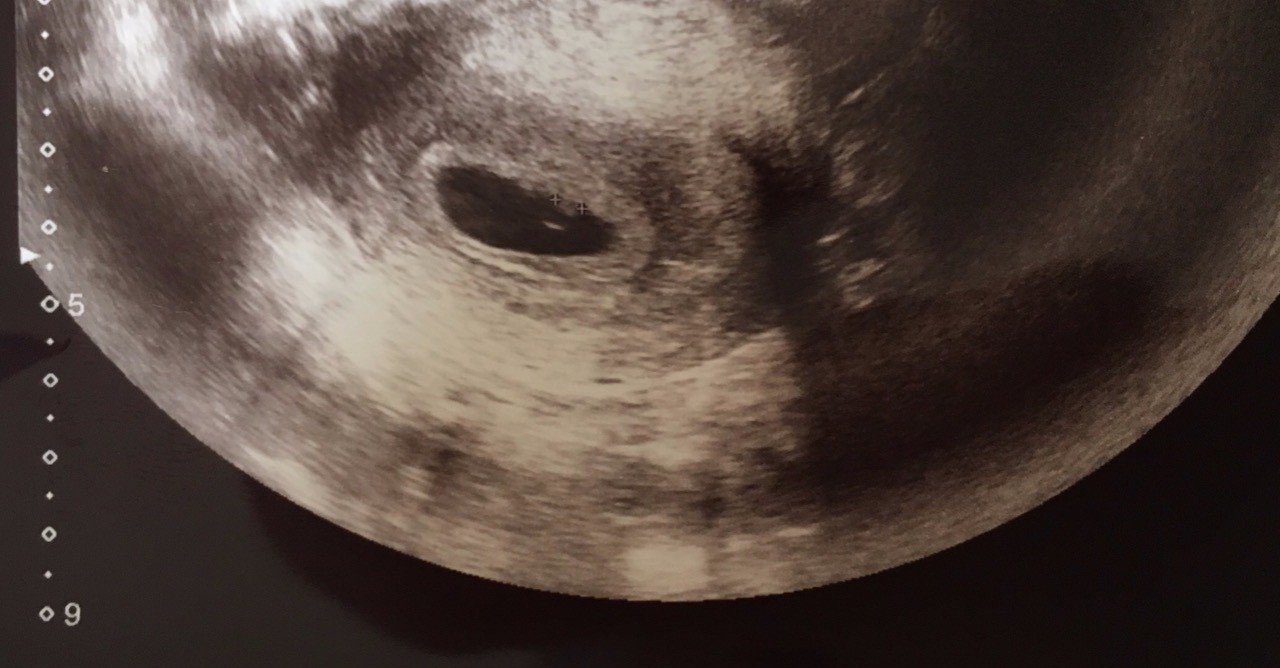

4週5日のエコー写真です! 前回、初期流産をしてからの 妊娠なので、心拍が聞こえるまで あと12週間。心配でたまりませんが、 生命力を信じます! 胎嚢の大きさ74mmです♪4週後半〜5週前半で胎嚢が確認できず、採血判定となった方、その時のhCGの数値と妊娠週数を教えて下さい。 その後、胎嚢や心拍が確認できた方はいつ頃、確認ができましたか? 〜私の情報〜 5/2の段階で生理予定日から10日を過ぎたところです。 生理4週 ! ずいぶん早く行きましたね〜(*^^)私は7週に行ってgs( 胎嚢 )=247ミリとなっていました。 この時のcrlはまだ表示がなかったです。先生からは、2週間後にまた来てねって言われて、予定日とか

妊娠4週5日 4w5d の超音波 エコー 写真